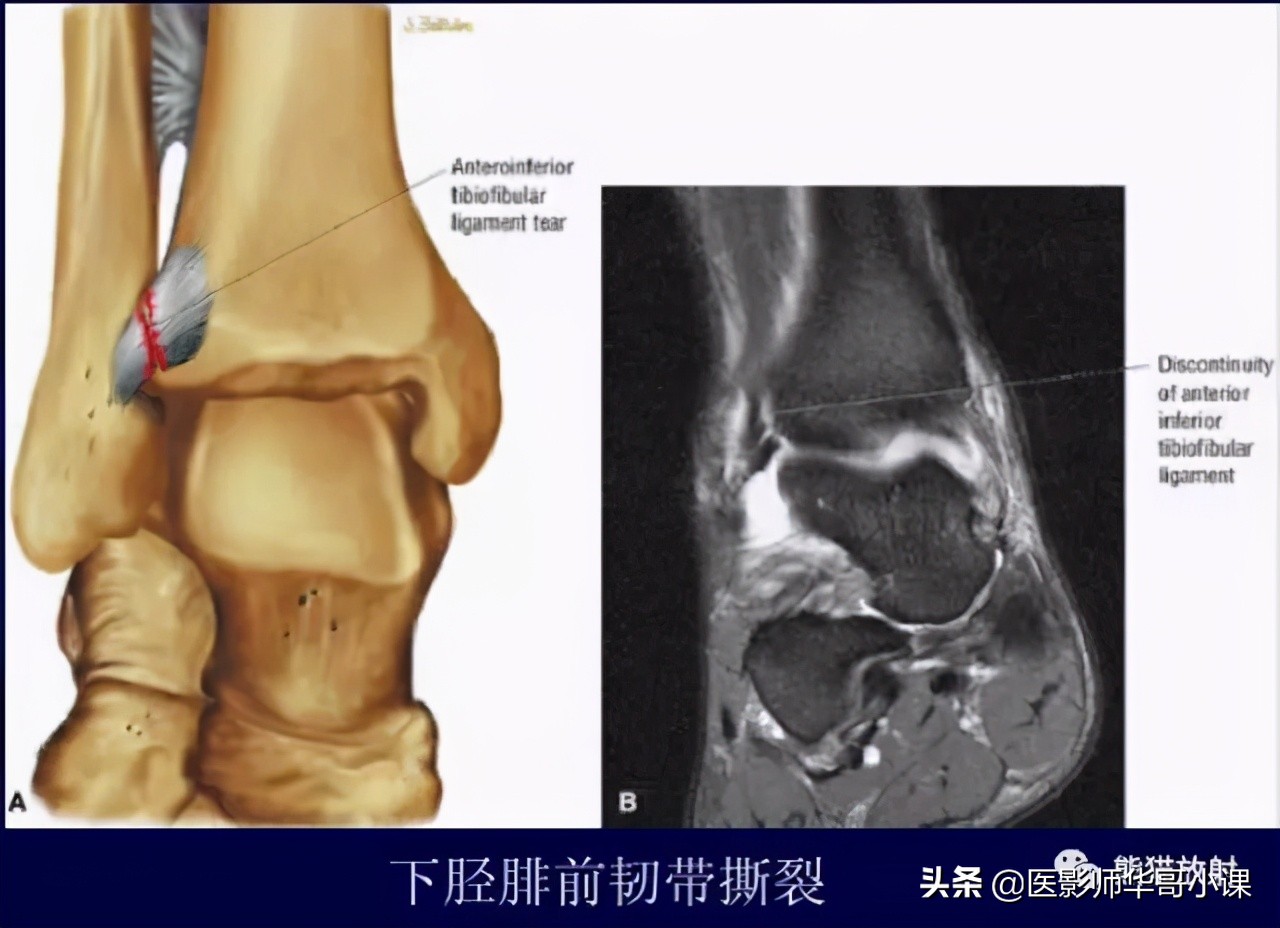

下胫腓联合韧带

胫腓骨远侧关节面由腓骨远端的凸面和胫骨远端的凹面组成,由胫腓韧带链接,关节内无软骨结构。 远端胫腓联合韧带由四部分韧带组成,包括: 骨间韧带,下胫腓前韧带,下胫腓后韧带,下横韧带。

骨间韧带由骨间膜远端增厚形成。下胫腓前韧带起于胫骨结节的前外侧,止于腓骨脊的前侧。下胫腓后韧带起于胫骨脊后侧,止于外踝后缘。下横韧带组成下胫腓后韧带的下半部分,可视为下胫腓后韧带的一部分。

下胫腓前韧带(35%),下胫腓后韧带深层(33%)对踝关节稳定性作用最大,其次是骨间膜(22%)和下胫腓后韧带浅层(9%)。

下胫腓联合韧带损伤的机制 通常是踝关节外旋和过度背屈。可以导致下胫腓联合损伤的运动包括运动(足球等),低能量创伤等。外旋损伤通常发生于踝关节旋前或旋后位。胫腓联合韧带损伤可以单发或者合并骨折。